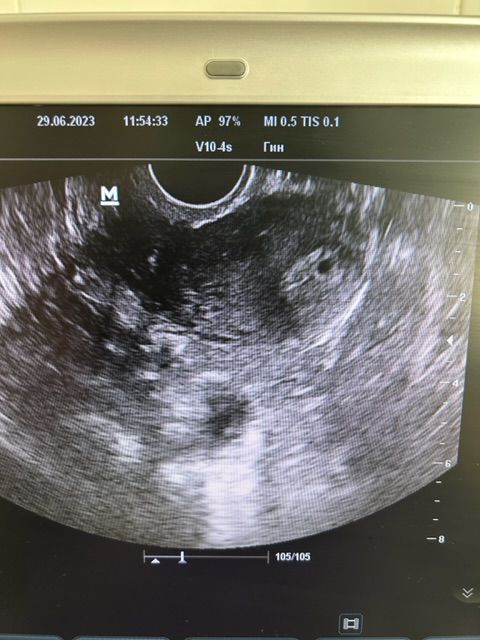

25.06 утром мне берут оак, бх, хгч, мочу. А вечером у меня поднимается температура 38.1. Ставят капельницу с парацетамолом. Падает до 37. Через час поднимается опять 38. Делают литичку. Папаверин, димедрол, анальгин. Вырубаюсь спать. Утром 26.07 как ни в чем не бывало. Только понос) делают УЗИ на двух аппаратах - в матке ничего не видят. Зато думают, что солидное образование в яичнике 14х15х13 - это плодное яйцо с зб. Напоминаю, яйцо без динамики по кровотоку и размерам с 16.06. Т.е за 10 дней не изменилось. Я спрашиваю может ли это быть кистой желтого тела, мне говорят, что может. Но больше похоже на плодное яйцо. Договариваемся ждать хгч 1000. Очень ждем результат от 25.06. Вечером 26.06 опять повышение температуры до 37,9. Самостоятельно падает до 37,3.